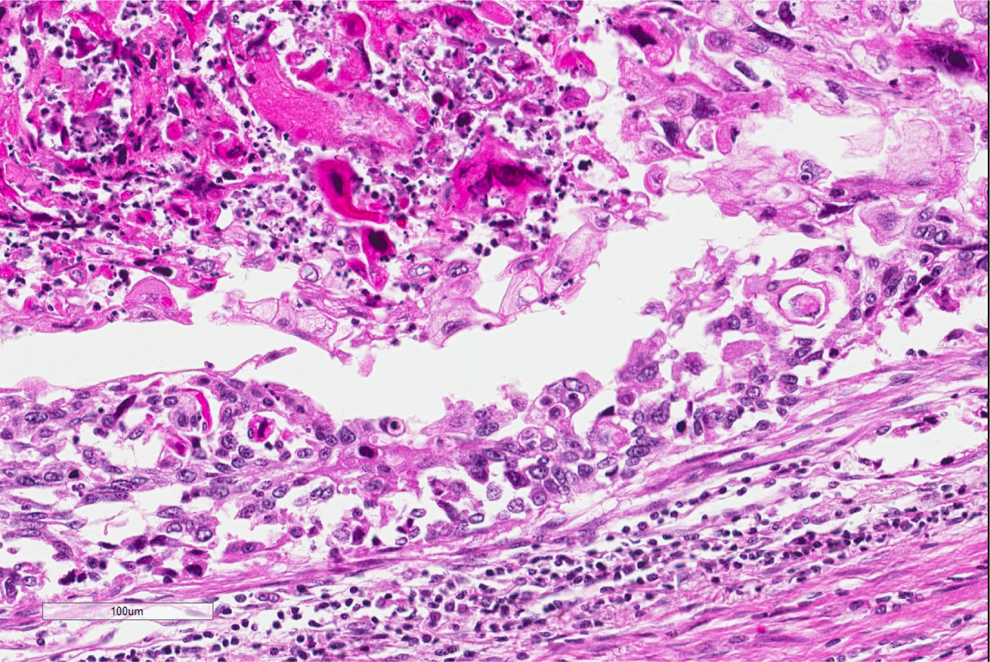

A biopsy was performed because of the high clinical suspicion of a malignant lesion. Figures 1 to 3 show representative histologic features of the biopsy on low, medium, and high power.

High power of another area of tumor cells showing many keratinized tumor cells that are hyperchromatic and eosinophilic.

The diagnosis, based on the morphologic features, is squamous cell carcinoma. On low power, there are multiple infiltrating nests of tumor cells, as well as a large area of necrosis in the upper right corner (Figure 1). On intermediate magnification (Figure 2), one can recognize sheets of polygonal cells with a high nuclear to cytoplasmic ratio, hyperchromatic and pleomorphic nuclei on the bottom and left of the image, and large keratinizing and atypical cells within the necrotic area on the upper right. Keratinization can be in the form of keratin pearls or as deeply eosinophilic dyskeratotic malignant cells (Figure 3). If one observes intercellular bridges between the polygonal cells, this can be helpful in confirming squamous cell carcinoma.